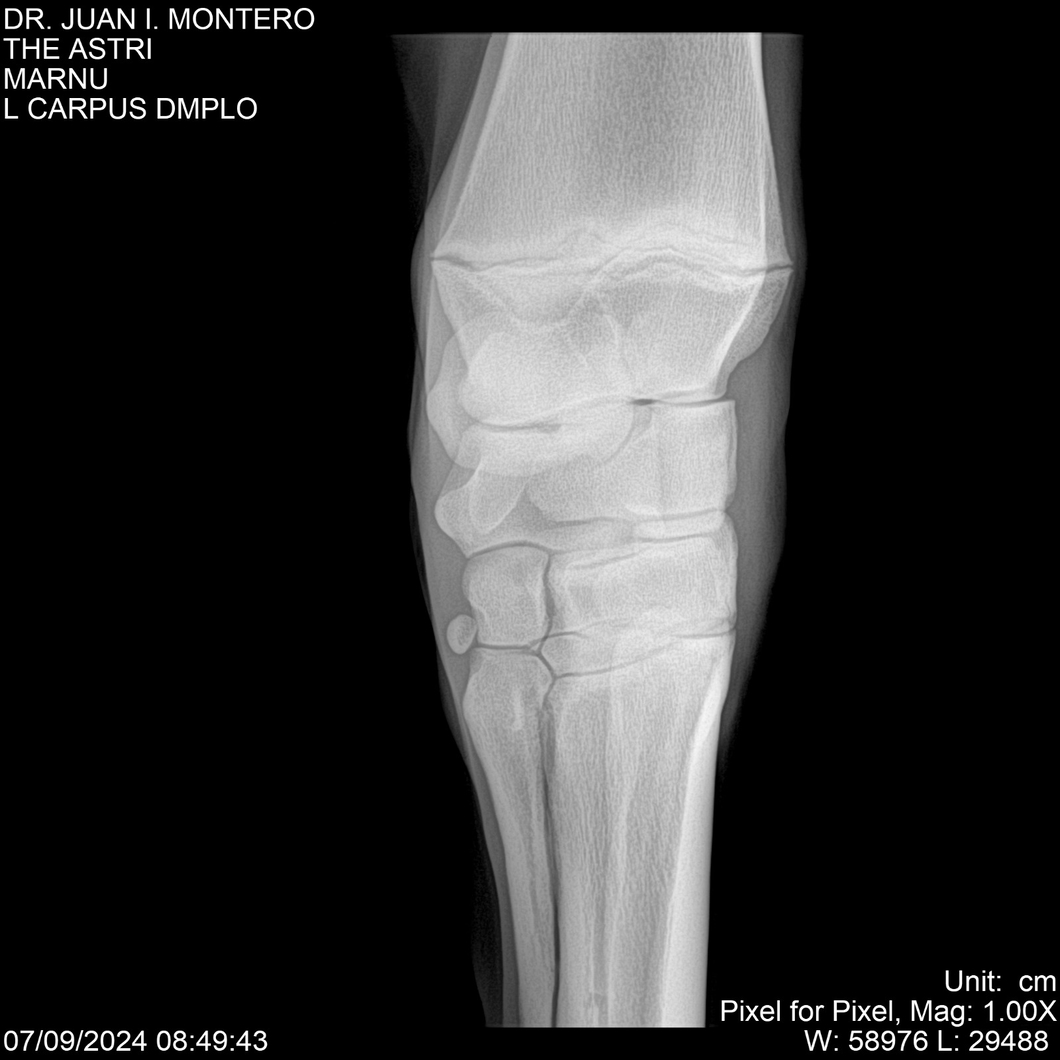

LOTE 10, THE ASTRI Lote Anterior Volver al remate Lote Siguiente Ficha Contacto Montevideo - Ficha del Lote Identificador: #282514 Categoría: Yeguarizos Montevideo - 60 Visualizaciones ClicData Contacto Empresa: Abelenda N. R., Walter Hugo Nombre*: Teléfono* : E-mail* : Mensaje Enviar Registrese gratis Este contenido Exclusivo está disponible sólo para usuarios registrados Ingresar